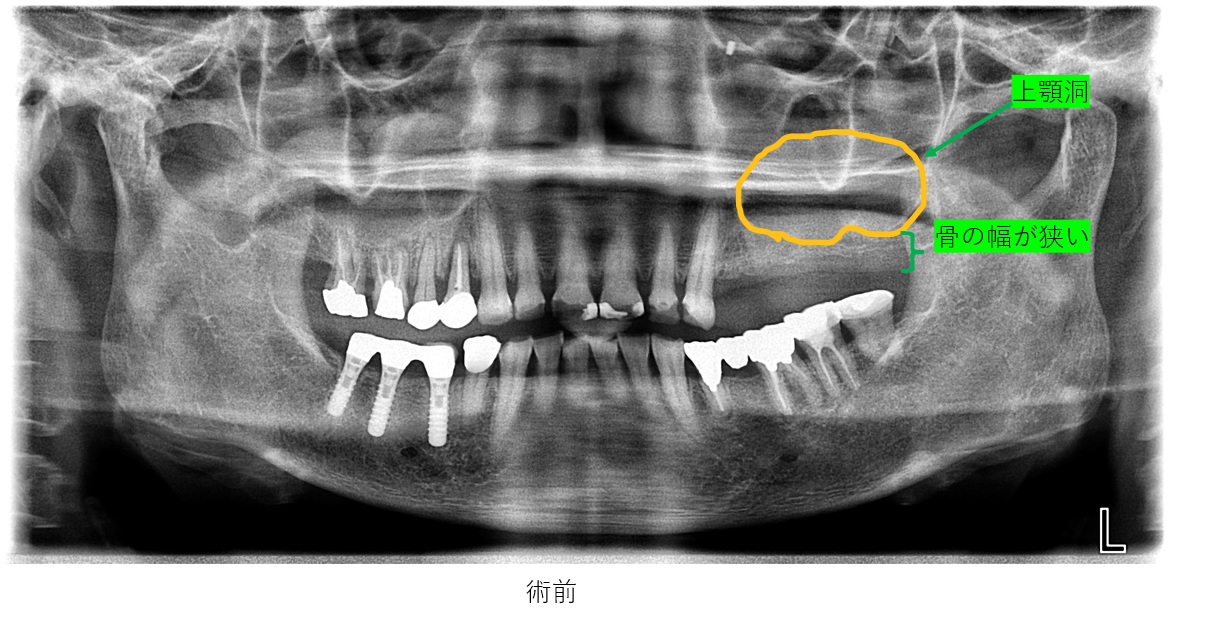

初診時のレントゲンも診ると

左上の骨が幅が狭い状態です。上顎洞が下に降りており、インプラントは困難です。

なぜなら、インプラントを埋入するには、骨が十分にある事が必要です。

左上の図の黄色部位が上顎洞です。

上顎洞が大きく、上顎洞の下部にほどんと、骨が無い状態と歯が喪失している状態を示しました。

基本、インプラントは骨に埋入して、骨とインプラント本体が結合する事で、重要です。

ベースとなる骨が無い部位へのインプラントは、不可能です。